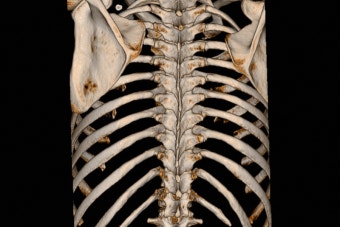

갈비뼈 골절은 늑골(갈비뼈)이 충격으로 인해 금이 가거나 부러진 상태를 말합니다. 우리 몸의 흉곽은 비교적 단단하지만, 예상치 못한 강한 힘을 받게 되면 골절이 발생할 수 있습니다.

전문의의 X-ray 또는 CT 진단을 통해 결정됩니다.